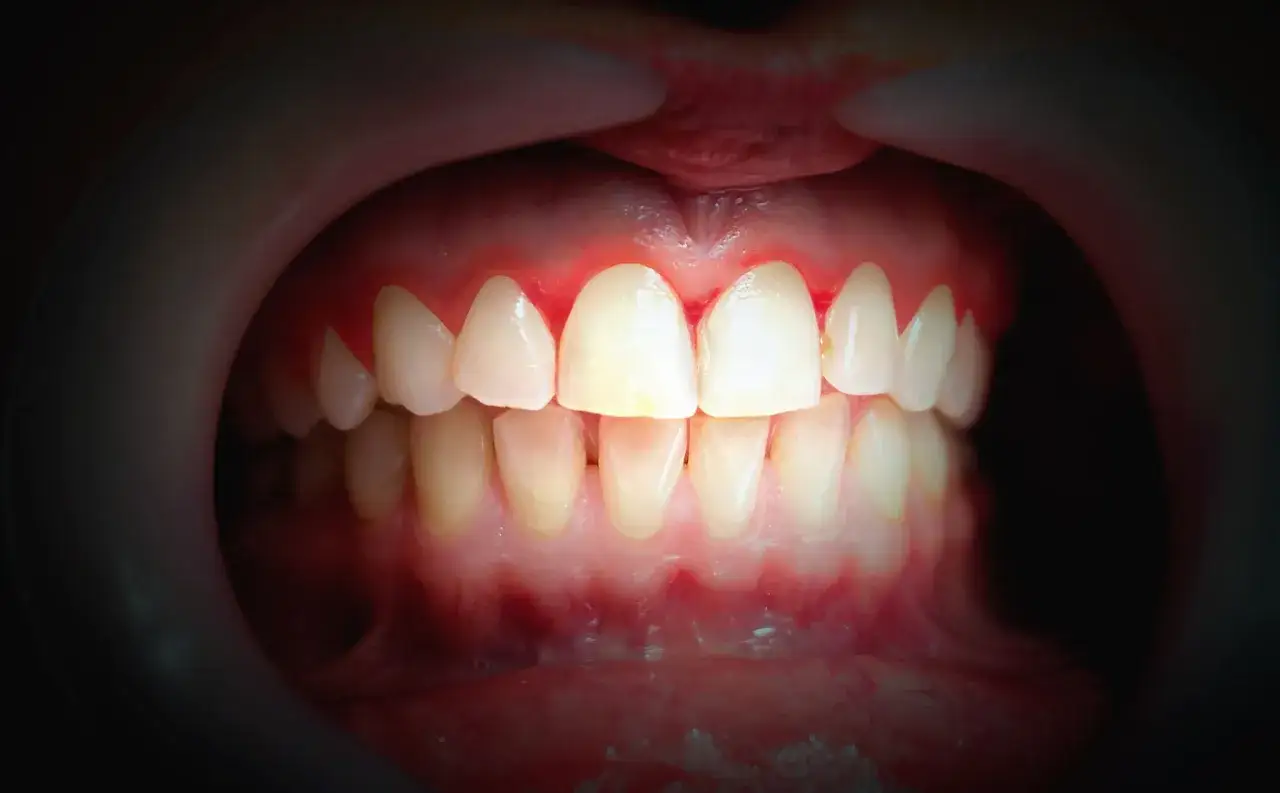

Krwawienie dziąseł, nieprzyjemny zapach z ust i obrzęk

Najczęstszym i często pierwszym zauważalnym objawem jest krwawienie dziąseł – podczas szczotkowania, nitkowania, a nawet jedzenia twardych pokarmów. To sygnał, że dziąsła są w stanie zapalnym. Inne wczesne objawy to obrzęk, zaczerwienienie i tkliwość dziąseł. Zdrowe dziąsła powinny być różowe, jędrne i nie powinny krwawić. Dodatkowo, wielu pacjentów z paradontozą skarży się na nieświeży oddech (halitozę), który jest często wynikiem aktywności bakterii beztlenowych w kieszonkach dziąsłowych. Ten nieprzyjemny zapach utrzymuje się mimo regularnej higieny i jest wyraźnym sygnałem problemu.

Odsłanianie szyjek zębowych, kieszonki i ruchomość zębów

W miarę postępu choroby pojawiają się bardziej zaawansowane objawy. Jednym z nich jest recesja dziąseł, czyli odsłanianie się szyjek zębowych. Zęby wydają się wtedy dłuższe, a ich korzenie mogą stać się wrażliwe na zimno, ciepło lub dotyk. Podczas badania dentysta może wykryć głębokie kieszonki dziąsłowe, które są wyraźnym znakiem postępującej paradontozy. W późniejszych stadiach choroby, gdy dochodzi do znacznego zaniku kości, pacjent może zauważyć ruchomość zębów, a nawet ich przemieszczanie się lub rozchylanie. To już bardzo zaawansowany objaw, który świadczy o poważnym uszkodzeniu aparatu zawieszeniowego zęba i wymaga pilnej interwencji.